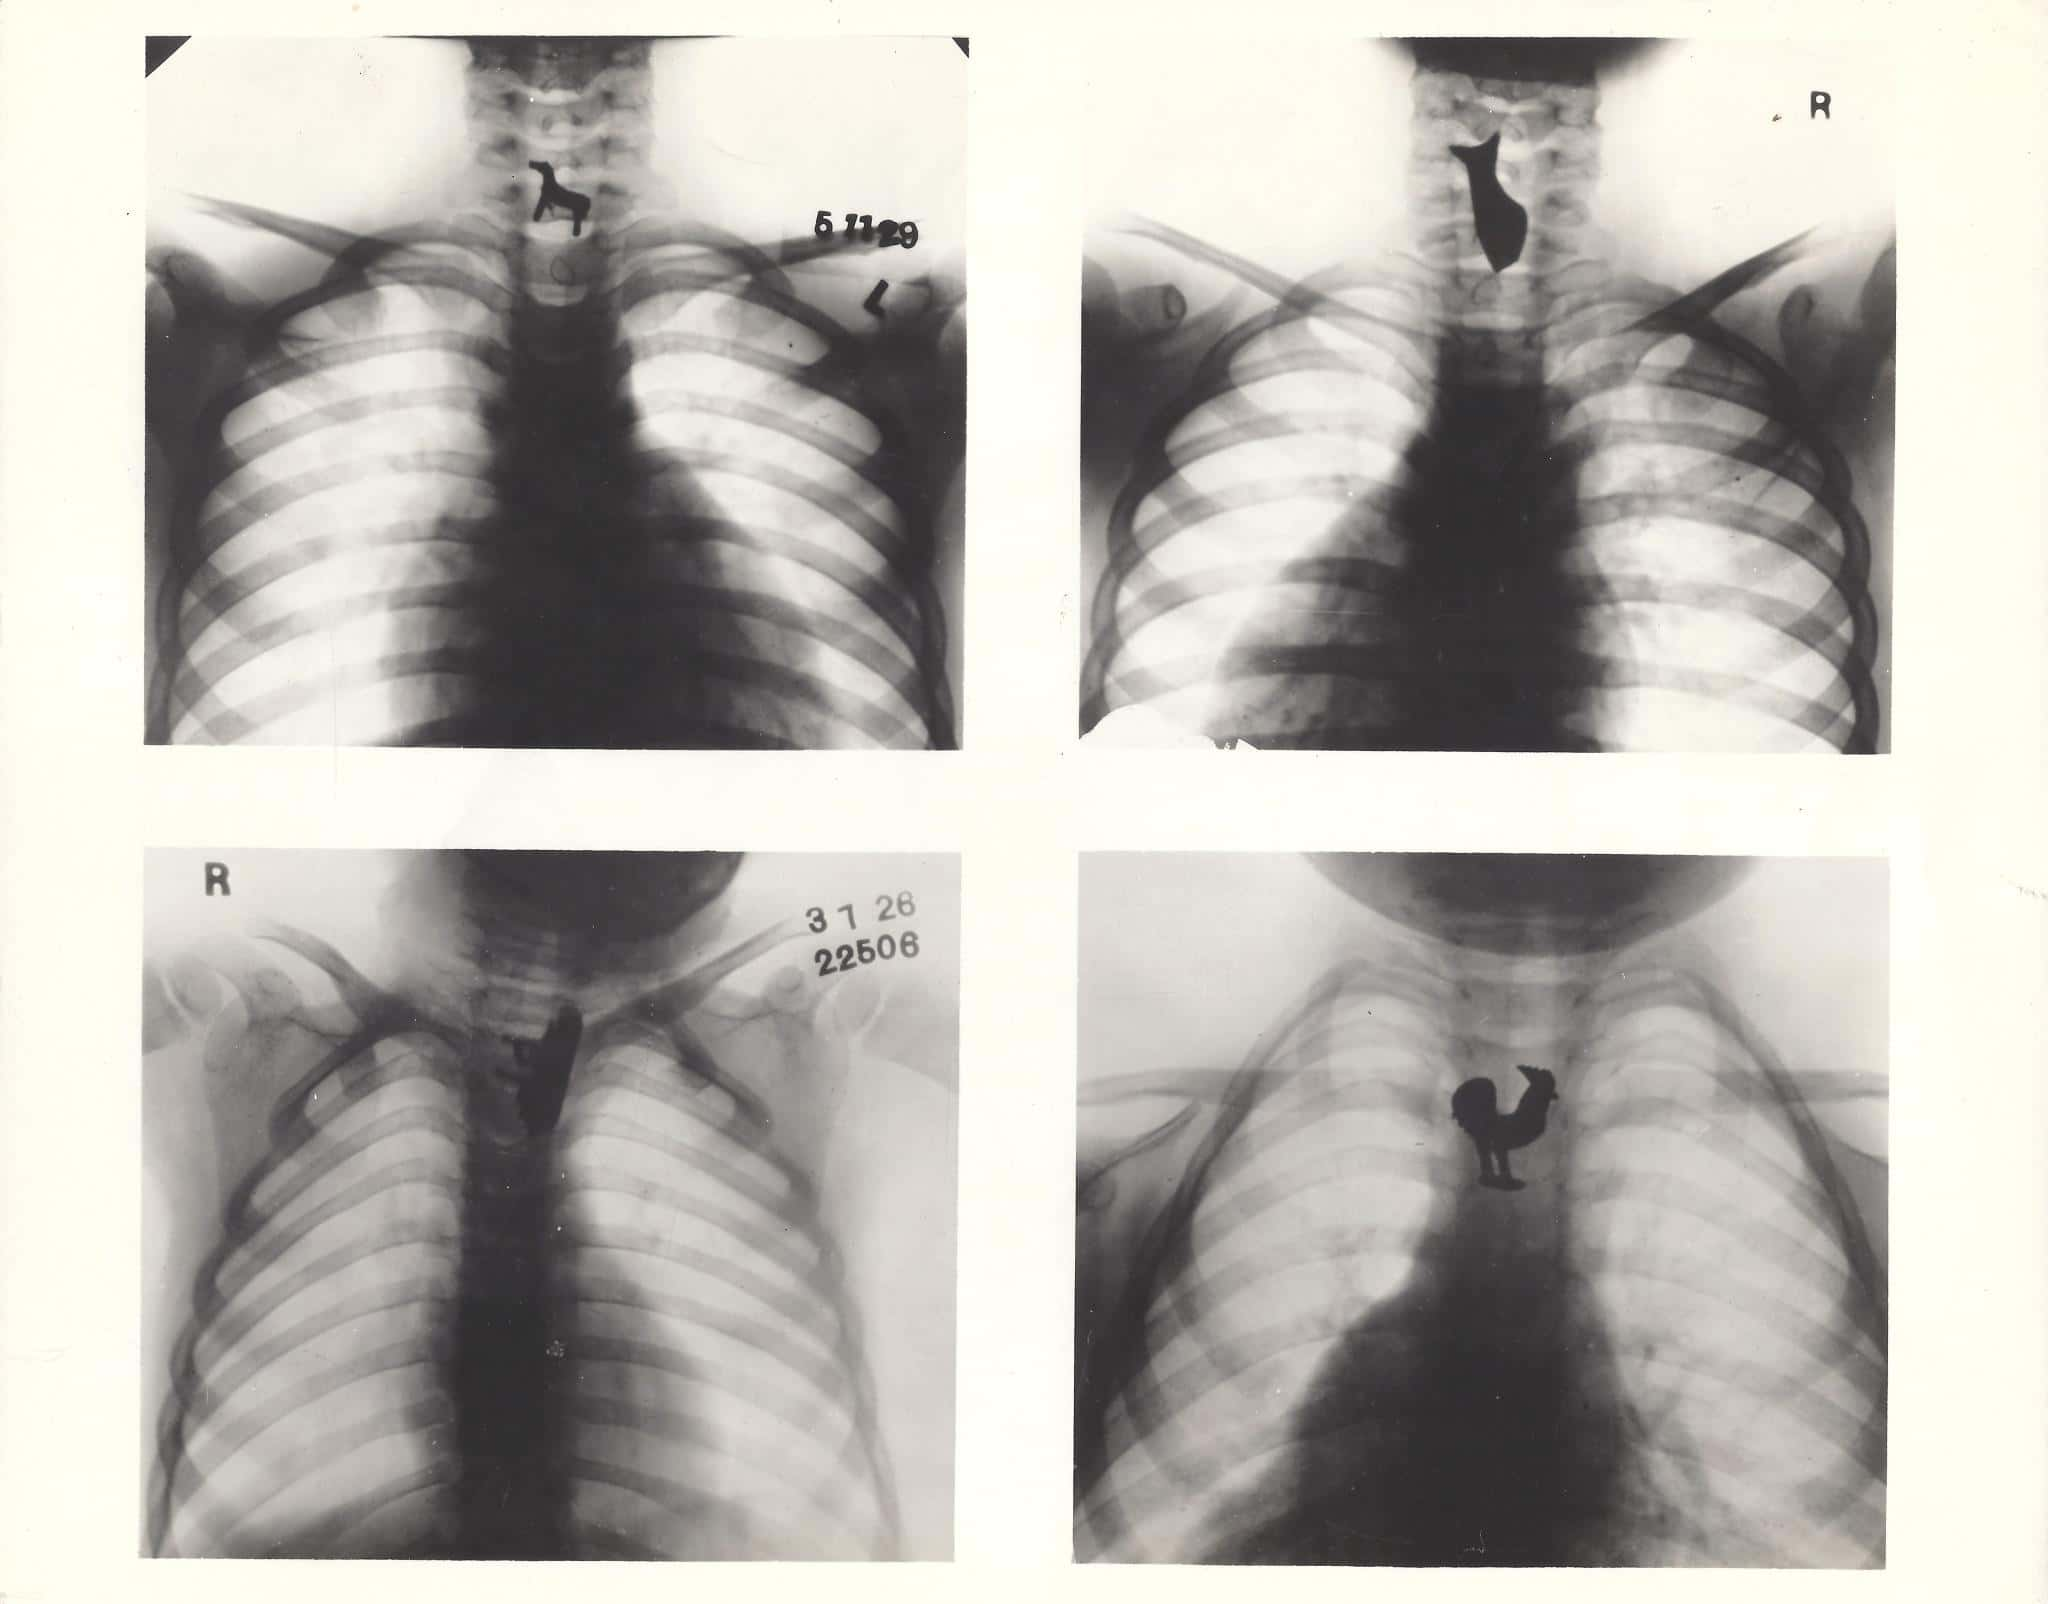

#1 Just Like That Scrubs Episode

I had a patient refuse to admit he swallowed a pen, even though an X-ray showed the pen in his small bowel. We took the pen out during emergency surgery. It's funny because I literally just watched the Scrubs episode where Turk and his colleagues were looking at X-rays and laughing at all of the stuff that people put in their bodies and wound up in the emergency room for.

#16 Kid's Lie About The Darndest Things

Whilst I was working in general surgery we had a 14-year-old kid come in with a small bowel obstruction. The X-ray showed this huge circular object in his bowel and we just couldn't work out what it could be, so he went in for open surgery to take it out. When we opened him up we found a fully intact water balloon, filled up and tied. When he woke up when we asked him why he ate it. He said he "didn't remember eating a water balloon." No idea how you could forget it though.